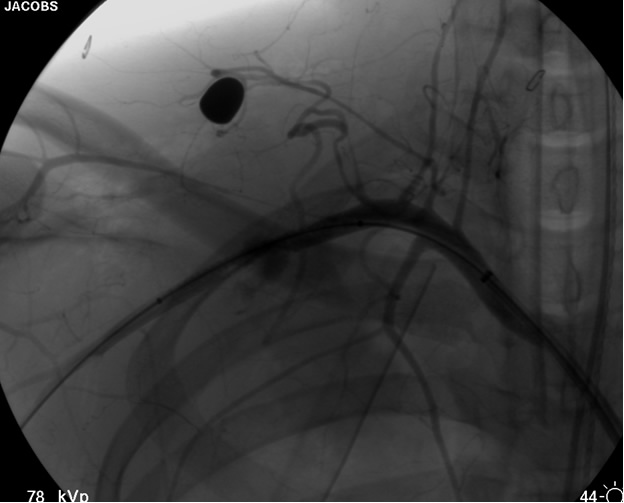

transected artery visualizing the pseudoaneurysm (Figure 2). A Viabahn covered stent (W.L. Gore & Associates, Flagstaff, AZ) is chosen for the appropriate size of the native vessel being careful not to oversize the stent graft. The stent graft is advanced across the lesion. Selective angiograms through the sheath may be performed to choose correct placement and appropriate landing zones. The stent graft is deployed under fluoroscopic visualization. Next, we utilize an appropriate sized 10 mm low pressure balloon to “iron out the edges” of the stent and bring it up to profile of the artery (Figure 3). Next, completion angiograms are performed to rule out endoleak and complete exclusion of the pseudoaneurysm, as well as to confirm distal runoff to the forearm and palmar branches of the extremity (Figure 4).

![]() |

| Figure 4: Post-deployment of the stent with 10 mm balloon brought up to vessel profile. |

Sheath and wire are pulled back into the iliac artery under fluoroscopic visualization. After an appropriate “sheath shot” angiogram to delineate correct placement of the arterial puncture, the sheath is changed out to an 8F Angioseal ® (St. Jude Medical Inc. St. Paul, MN) closure device.